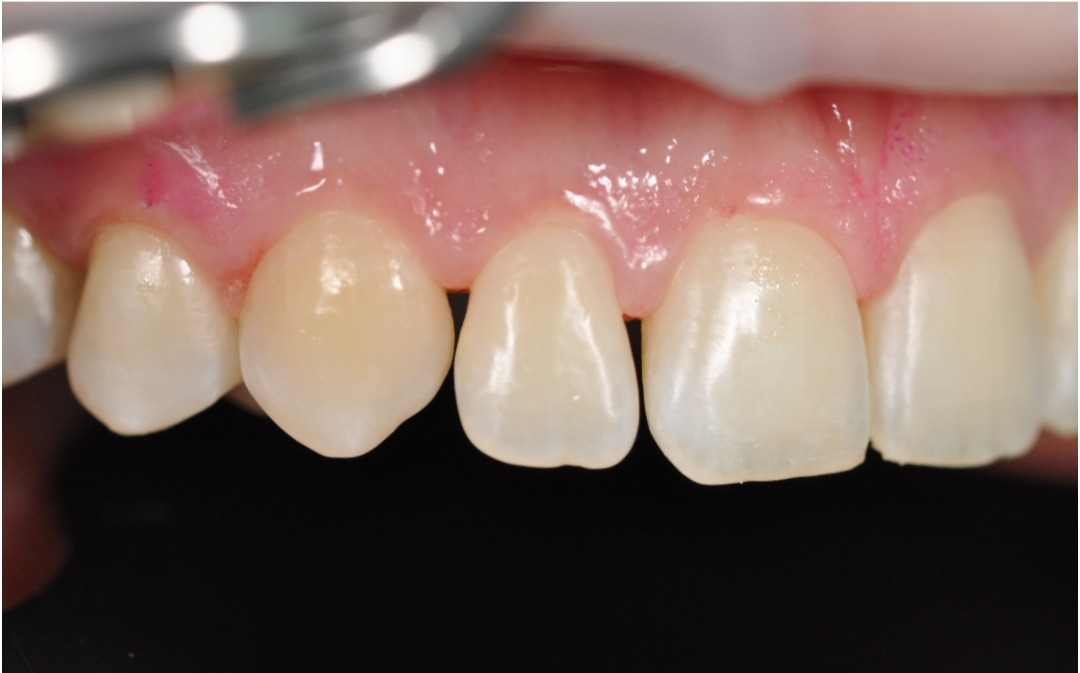

Этап №4

Финишная реставрация.

После снятия брекет-системы стоматолог-терапевт провела художественную реставрацию формы боковых резцов, добившись идеальной гармонии и естественности улыбки.